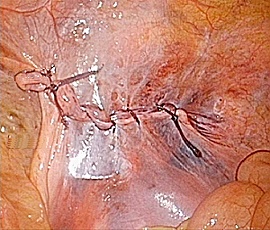

手術画像